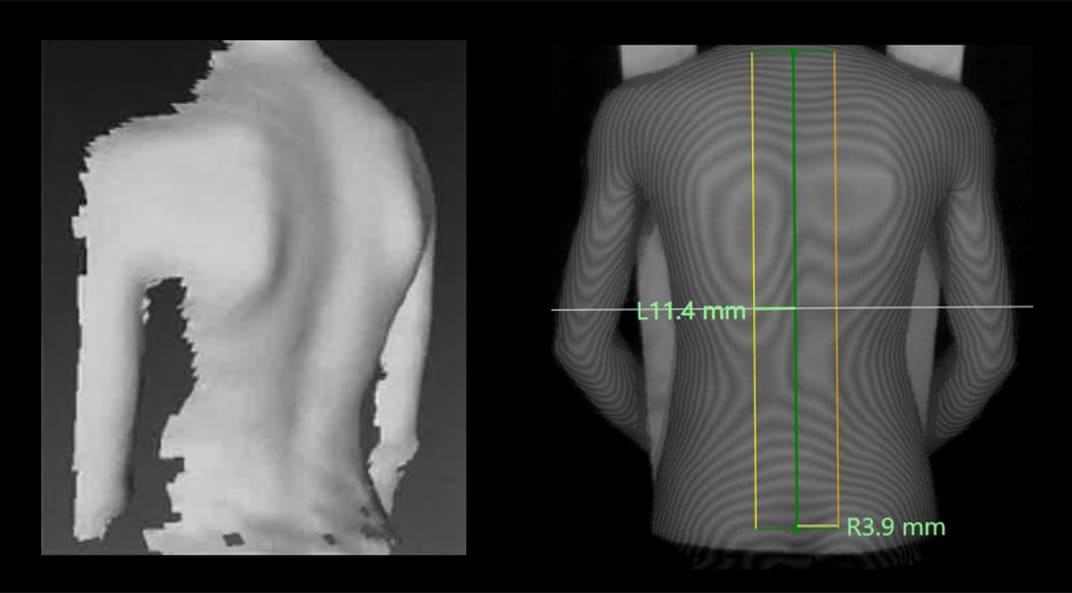

Our radiation-free screening system, powered by advanced 3D surface scanning, captures a detailed image of the back in just one second. By converting surface deformities caused by spinal rotation into precise 3D data, we achieve millimeter-level quantitative evaluation. This technology detects mild cases invisible to the naked eye and simplifies tracking progression over time. For physicians, it serves as an effective triaging tool, identifying cases that truly require X-ray imaging and improving overall diagnostic accuracy. For students and parents, the process is painless and stress-free. Its compact, lightweight design allows for seamless integration into school screenings and community health checkups, making consistent monitoring throughout adolescence a practical reality.

Body Surface Data Captured by Senaka Scan